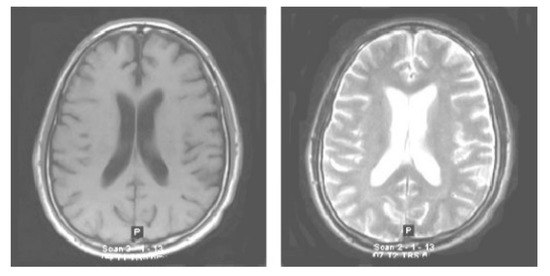

3.1. Acquisition of an Image

The very first stage of the suggested methodology is the acquisition of an image, in which an MRI image is used as an input for processing. In the application of the suggested methodology, brain tumor MRI images have been used. Four datasets containing T1-w and T2-w contrast-enhanced MRI images of three kinds of brain tumors were used. Images in the MRI format are stored in MATLAB R2021a, 255 × 255 in size, and they are shown as RGB images of grayscale as the ranges of their entries are from 0 to 1. Here, the black image is represented by 0 while the white image is represented by 1. Entries between 0 to 1 represent the variation in intensity from black to white (see Figure 2).

Figure 2.

Original normal brain T1-weighted and T2-weighted MRI images.